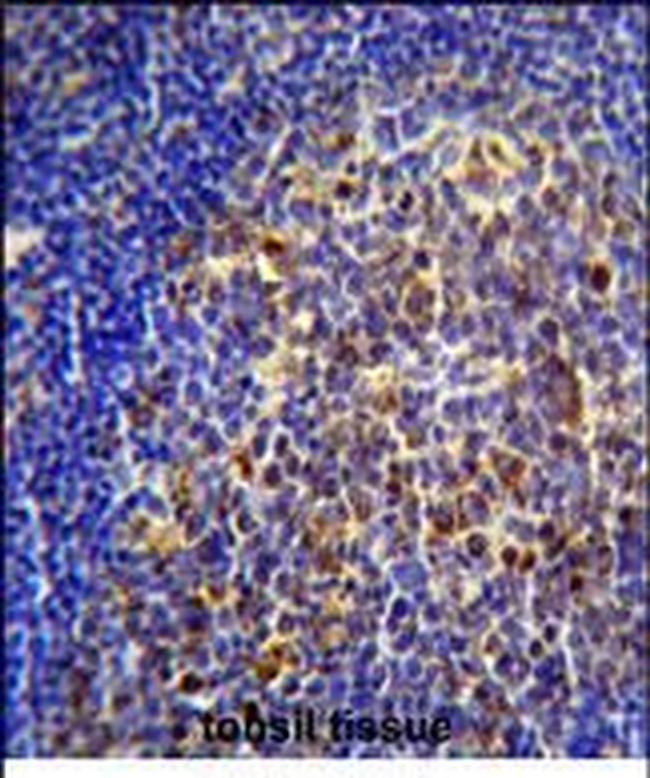

- Main image

- Experimental details

- Immunohistochemical analysis of CHRNA10 in formalin fixed and paraffin embedded human tonsil tissue. Samples were probed with a CHRNA10 polyclonal antibody (Center) (Product # PA5-48341) followed by peroxidase conjugation of the secondary antibody and DAB staining.